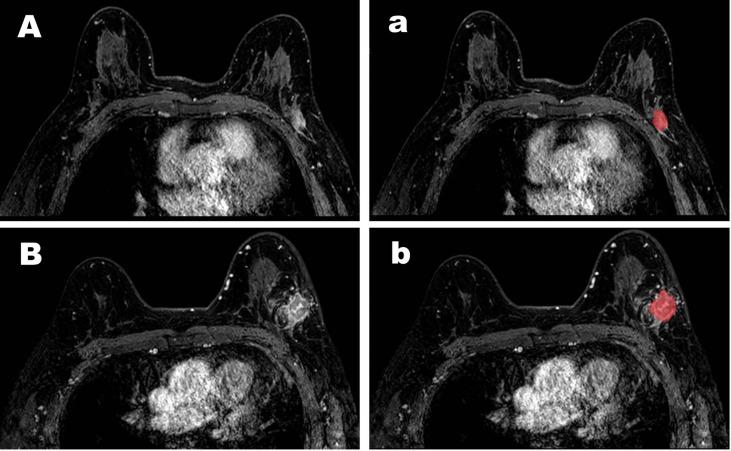

A Clinical Assessment of a Magnetic Resonance Computer-Aided Diagnosis System in the Detection of Pathological Complete Response After Neoadjuvant Chemotherapy in Breast Cancer.

This study aimed to assess the diagnostic performance and the added value to radiologists of different levels of a computer-aided diagnosis (CAD) system for the detection of pathological complete response (pCR) after neoadjuvant chemotherapy (NAC) in patients with breast cancer. Besides, to investigate whether tumor molecular typing is associated with the efficiency of diagnosis of the CAD systems.

470 patients were identified with breast cancers who underwent NAC and post MR imaging between January 2016 and March 2019. The diagnostic performance of radiologists of different levels and the CAD system were compared. The added value of the CAD system was assessed and subgroup analyses were performed according to the tumor molecular typing.

Among 470 patients, 123 (26%) underwent pCR. The CAD system showed a comparable specificity as the senior radiologist (83.29% vs. 84.15%, p=0.488) and comparable area under the curve (AUC) (0.839 vs. 0.835, p =0.452). The performance of all radiologists significantly improved when aided by the CAD system (P<0.05), And there were no statistical differences in terms of sensitivity, specificity and accuracy between the two groups with CAD assistance(p>0.05).The AUC values for identifying pCR in TN patients were significant (0.883, 95%CI: 0.801-0.964, p < 0.001).

The CAD system assessed in this study improves the performance of all radiologists, regardless of experience. The molecular typing of breast cancer is potential influencer of CAD diagnostic performance.